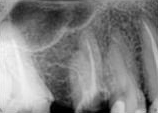

antes depois